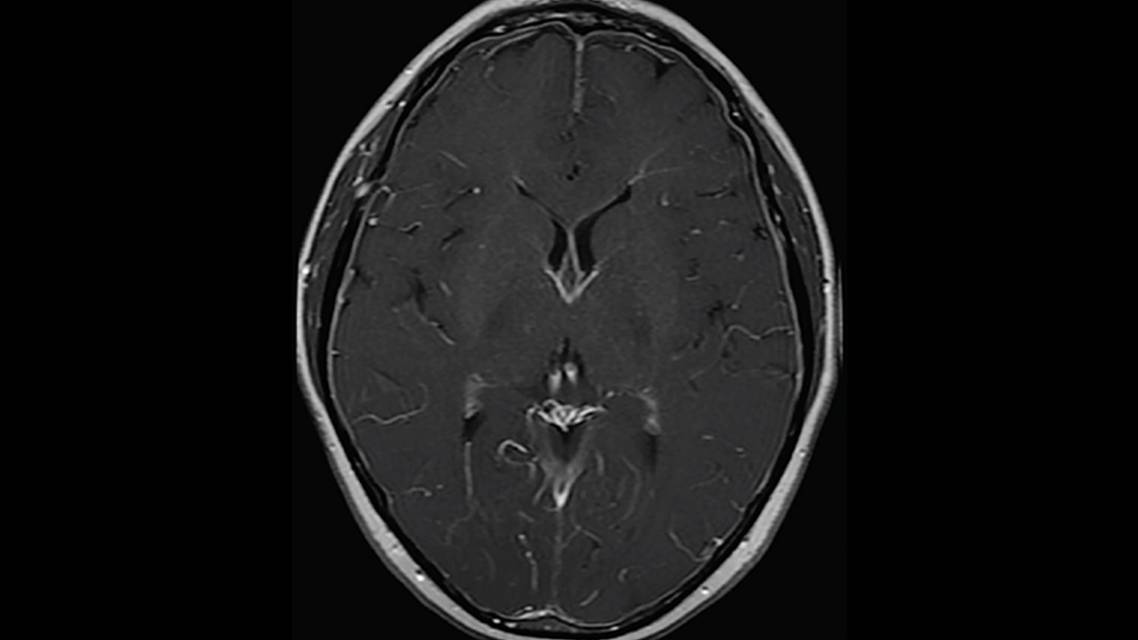

Before presenting to the neurology team, Mr. R was evaluated by the otolaryngology team (2 weeks earlier). The report from that visit shows a normal examination and normal audiogram. A brain MRI with and without contrast was done, and the report describes diffuse dural enhancement on T1 with contrast. A complex arachnoid cyst left of the falx cerebelli and a developmental venous anomaly of the right cerebellar hemisphere were also noted. Findings of Mr. R’s neurologic examination were normal, and spine MRI was ordered.

Brain MRI findings are seen in approximately 80% of people with SIH and most commonly show smooth and diffuse pachymeningeal (dura and arachnoid) enhancement (Figure), sagging of the brain with cerebellar tonsillar herniation, subdural fluid collection, enlarged venous sinuses, and pituitary enlargement. Spinal MRI may show dilated epidural veins and extradural or subdural fluid collection. Spinal CSF leak may also be confirmed with radioisotope cisternography, CT myelography, or MR myelography.4